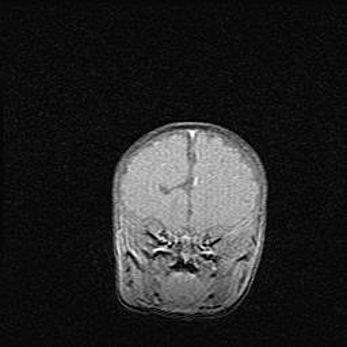

Мальформация Денди-Уокера. Киста задней черепной ямки.

Агенезия мозолистого тела.

Возраст: 2,5 месяца

Вес: 2420 г

Пол: женский

Окружность головы: 37 см

Срок гестации: 32 недели

Мальформация Денди—Уокера — редкий вид патологии ЦНС, представляющий собой врожденный порок развития каудального отдела ствола и червя мозжечка, ведущий к неполному раскрытию срединной (Мажанди) и латеральных (Лушка) апертур IV желудочка мозга. Для этогно синдрома характерна триада симптомов: гипотрофия червя мозжечка и/или полушарий мозжечка, кисты задней черепной ямки, гидроцефалия различной степени. В 70% случаев порок сочетается и с другими аномалиями головного мозга, в частности с агенезией мозолистого тела.